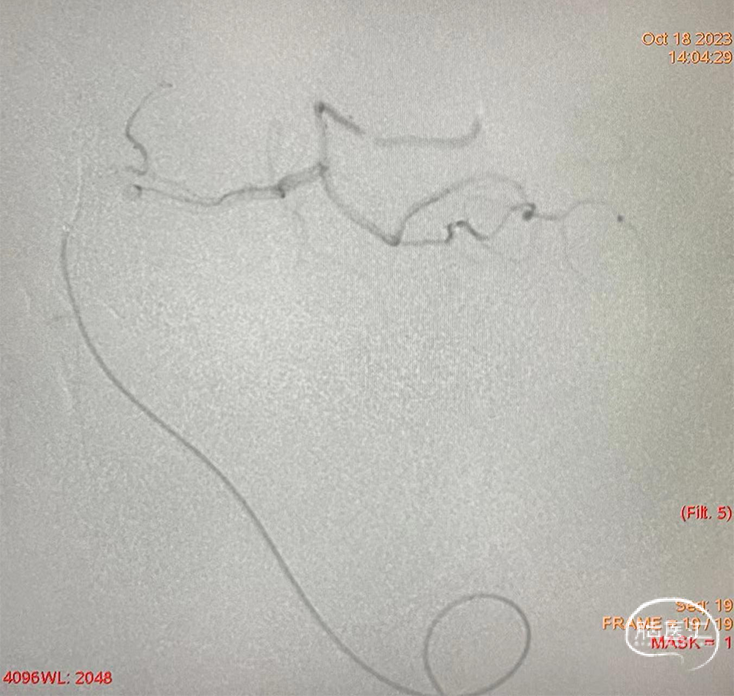

术前造影示:右侧椎动脉纤细,左侧椎动脉优势,起始部走形迂曲。

支架释放后,工作位造影血流通畅。